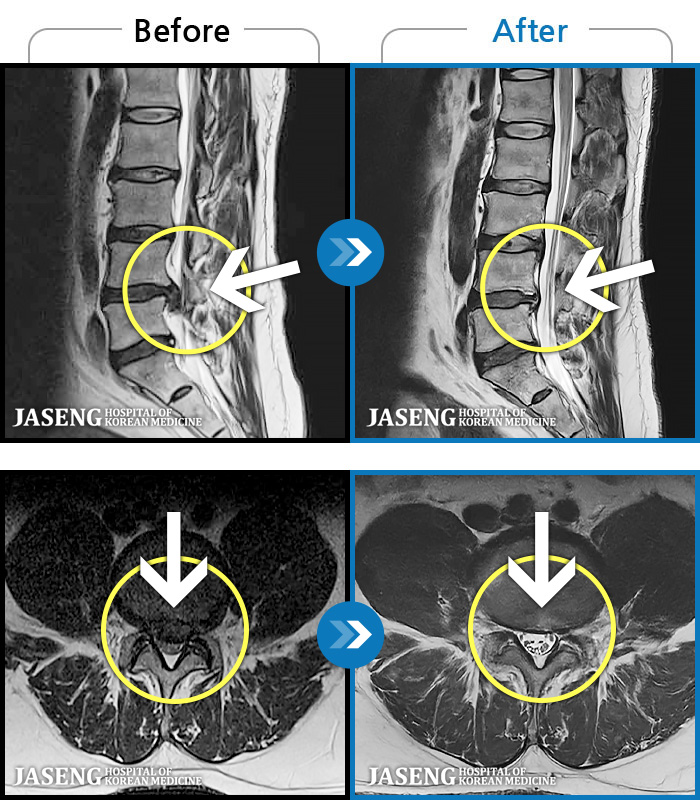

[ؿ] 24.10.10~25.04.23